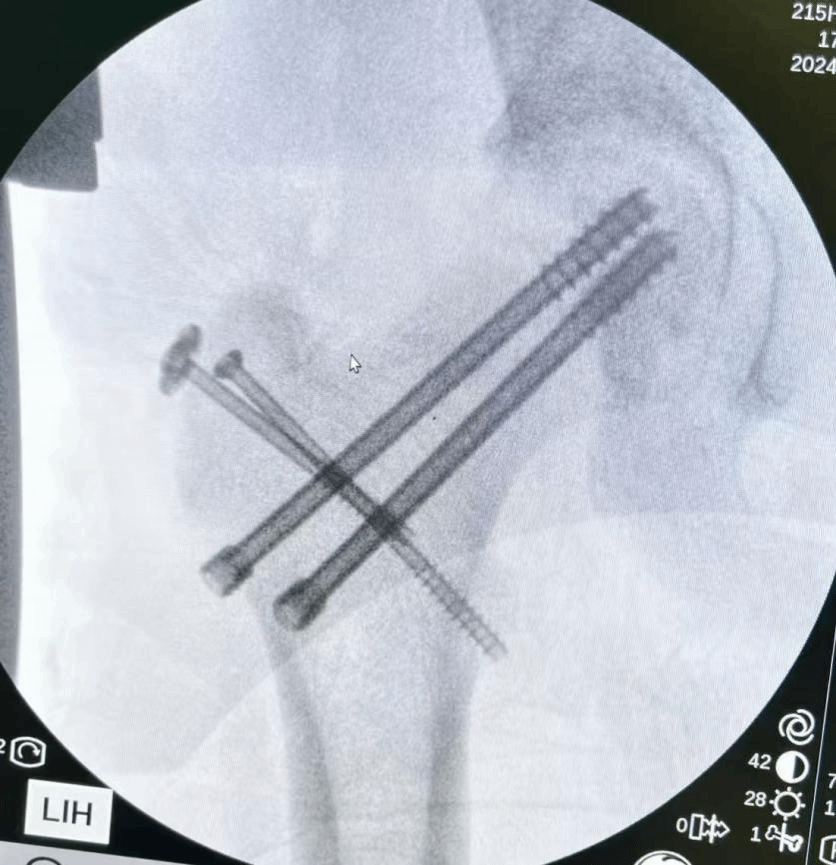

面对如此复杂且严重的伤情,潘主任立即组织全科进行讨论,在深入研究和综合分析,科室团队一致认为,经过股骨头骺端脱位出髋臼后侧,闭合复位不可行,应用外科脱位技术(SHD),既能最大程度保护骨折处血运、又能直视下复位,可吸收螺钉顺行固定后空心加压螺钉逆行加压固定,右侧股骨上段粉碎骨折应用青少年髓内钉固定。于是根据小张的具体情况,科室团队精心制定了一套科学、详尽的治疗方案。

作为一项新兴技术,SHD手术是近年来髋关节外科的里程碑式进步,特别是在保髋方面,是针对髋关节内病变相对“万能”手术入路,在髋关节创伤、髋关节良性病变的处理有极强的优势。SHD在儿童股骨颈头骺分离并脱位治疗中,将微创理念贯穿于治疗全过程, 在保证完全显露手术视野的前提下,最大程度地保护了股骨头最主要的血供来源,便于复位脱位的头骺,顺行+逆行固定,有效增强了固定的可靠性。

虽然这种损伤术后预后较差,但科室团队还是迎难而上,全力以赴。术中每一处血管、每一根神经的保护,每一个骨骺复位固定等细节,都对手术的成功及预后有着至关重要的影响。术前,潘主任团队反复研究手术的每一个步骤,尽力完善手术的每一个步骤与细节,力争做到完美。在小张生命体征平稳、颅内出血稳定后,11月25日,潘建宏主任团队按计划顺利完成手术,术后,在科室的精心照料下,小张顺利康复。